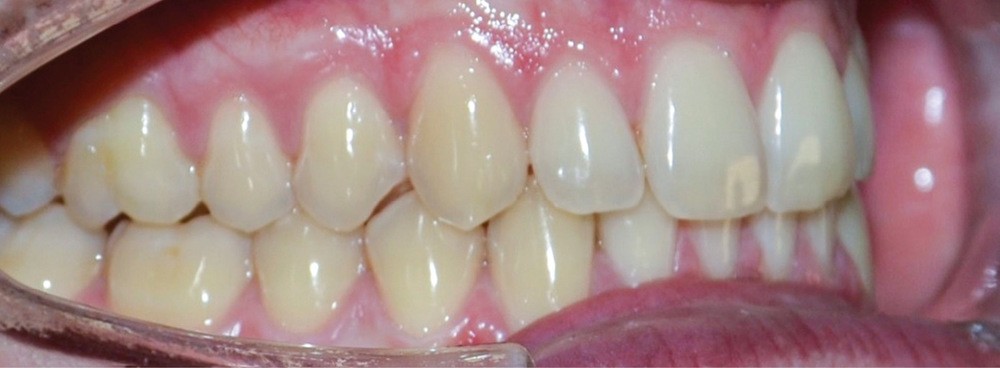

► L’entretien semi-directif met en évidence des signes d’apparition récente (un an environ), une aggravation progressive des symptômes, et la perception rapportée par le patient de moindres contacts occlusaux du côté gauche. L’examen clinique extra-oral révèle des douleurs musculaires lors de la palpation des muscles masséters, temporaux et ptérygoïdien médial gauche ainsi que des muscles sterno-cléïdo-occipito-mastoïdiens droit et gauche. Il n’y a pas de limitations d’ouverture buccale. L’examen clinique intra-oral révèle la présence d’une inocclusion dentaire gauche, qui s’étend des dents 23 à 27 (fig. 1 et 2). Il est à noter que la reprise de l’entretien ne rapporte pas d’antécédent de soins dentaires, orthodontiques et/ou prothétiques susceptibles d’engendrer une modification de l’occlusion.